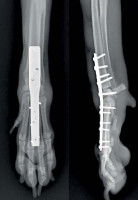

Qu’il s’agisse d’une arthrite septique ou non-septique, si la maladie est à un stade avancé et que la destruction des surfaces des articulations est trop importante, une arthrodèse est conseillée. Cette intervention chirurgicale, effectuée sous anesthésie générale, consiste à bloquer l’articulation touchée par l'obtention d'une fusion osseuse (en général de l'extrémité des os) dans le but de corriger une déformation ou d'obtenir l'indolence, c’est-à-dire l’insensibilité à la douleur. Elle est coûteuse (généralement plus de 1000 euros) mais prise en charge par l’assurance santé du chien, pour peu que l'on ait pris soin d’assurer son compagnon.